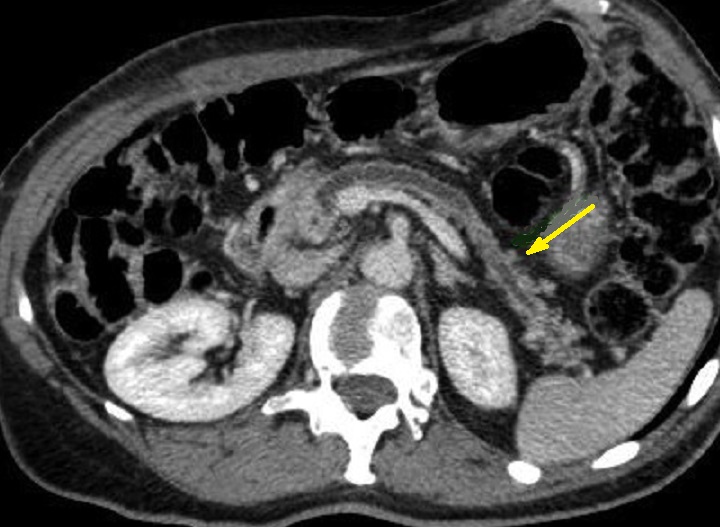

En cas tumeur cephalique ,

image radiologique de dilatation en amont du canal

pancreatique principale et des caneaux secondaires

parfois en se voyaient . Image radiologique TDM d'une

adenocarcinoma de la tete du pancreas avec effet de

dilatation legere en amont du CPP |

Une autre cas de tumeur

cephalique avec image de dilatation du canal

principale et atrophie parenchymateuse en amont du

pancreas . Image radiologique TDM en coupe axiale |